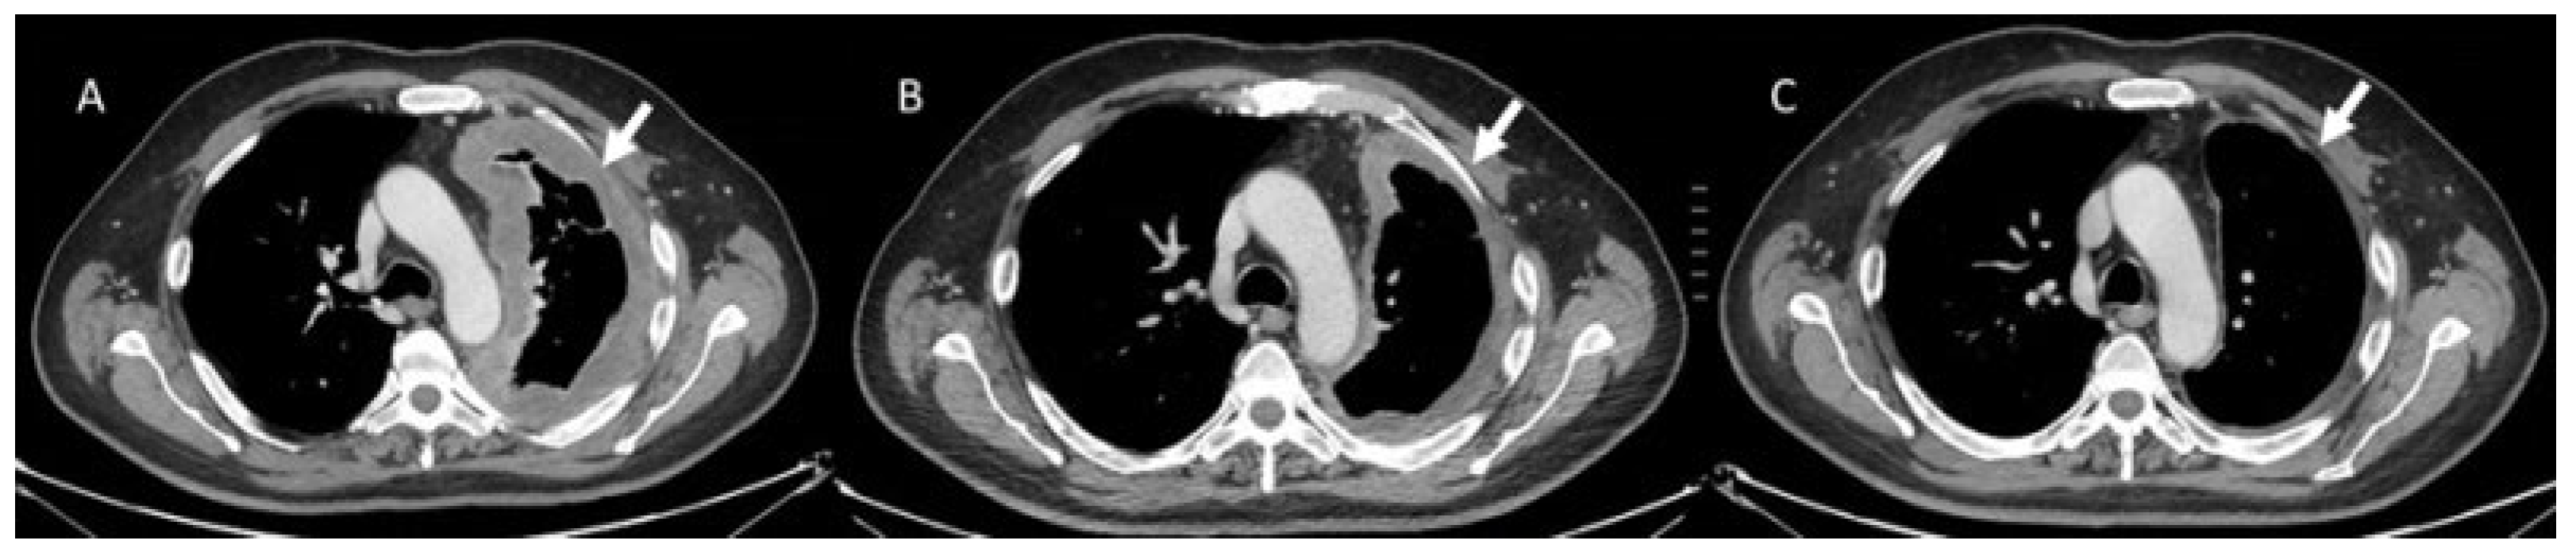

- Khunger, M.; Rakshit, S.; Pasupuleti, V.; Hernandez, A.V.; Mazzone, P.; Stevenson, J.; Pennell, N.A.; Velcheti, V. Incidence of Pneumonitis with Use of Programmed Death 1 and Programmed Death-Ligand 1 Inhibitors in Non-Small Cell Lung Cancer: A Systematic Review and Meta-Analysis of Trials. Chest 2017, 152, 271–281. [Google Scholar] [CrossRef] [PubMed]

- Kalisz, K.R.; Ramaiya, N.H.; Laukamp, K.R.; Gupta, A. Immune Checkpoint Inhibitor Therapy-related Pneumonitis: Patterns and Management. Radiographics 2019, 39, 1923–1937. [Google Scholar] [CrossRef] [PubMed]

- Delaunay, M.; Cadranel, J.; Lusque, A.; Meyer, N.; Gounant, V.; Moro-Sibilot, D.; Michot, J.M.; Raimbourg, J.; Girard, N.; Guisier, F.; et al. Immune-checkpoint inhibitors associated with interstitial lung disease in cancer patients. Eur. Respir. J. 2017, 50, 1700050. [Google Scholar] [CrossRef]

- Suresh, K.; Voong, K.R.; Shankar, B.; Forde, P.M.; Ettinger, D.S.; Marrone, K.A.; Kelly, R.J.; Hann, C.L.; Levy, B.; Feliciano, J.L.; et al. Pneumonitis in Non–Small Cell Lung Cancer Patients Receiving Immune Checkpoint Immunotherapy: Incidence and Risk Factors. J. Thorac. Oncol. 2018, 13, 1930–1939. [Google Scholar] [CrossRef]

- Tay, R.Y.; Califano, R. Checkpoint Inhibitor Pneumonitis Real World Incidence and Risk. J. Thorac. Oncol. 2018, 13, 1812–1814. [Google Scholar] [CrossRef]